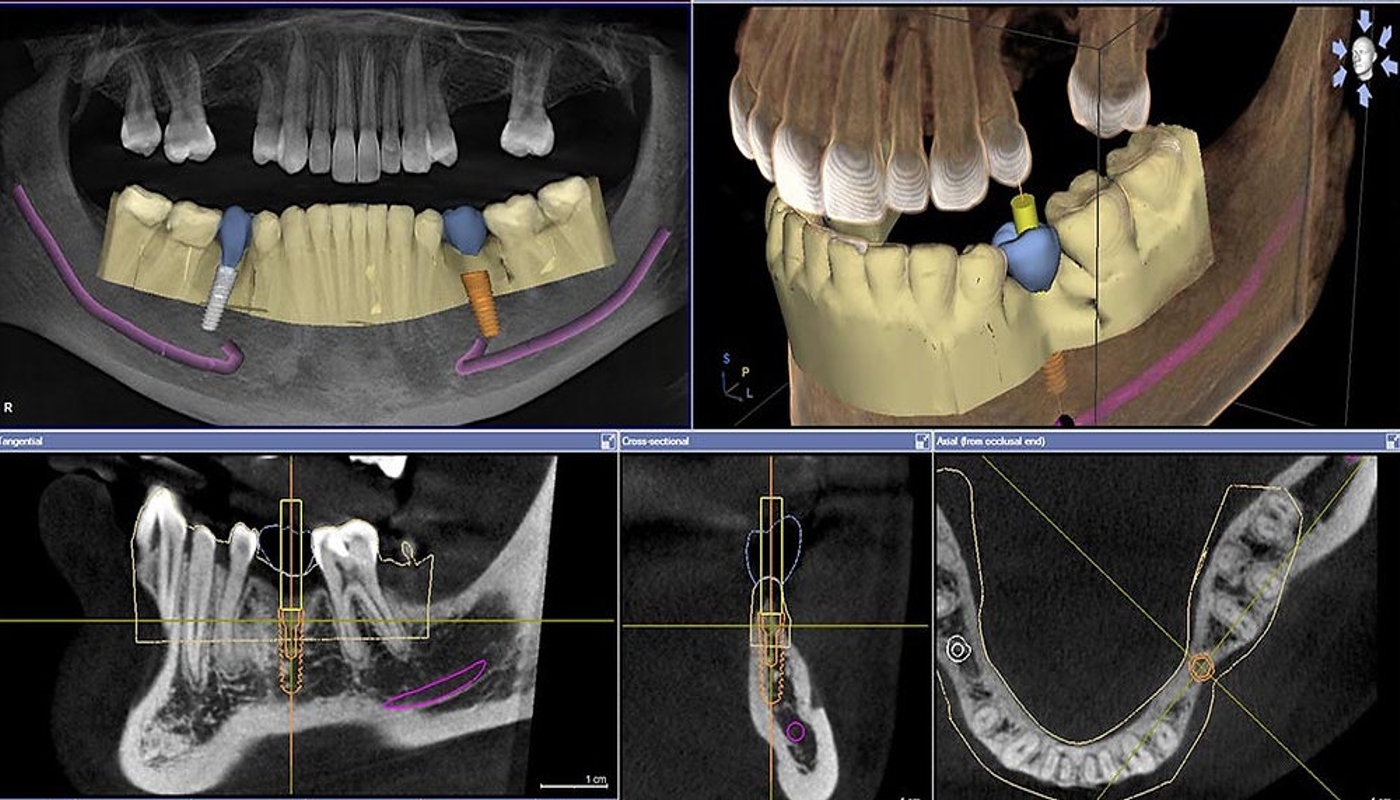

Nel nostro Studio Dentistico 2.0 adottiamo un approccio avanzato e personalizzato per l’implantologia, utilizzando tecnologie di ultima generazione come la TAC Cone Beam e lo scanner intraorale, che consentono una diagnosi digitale e una pianificazione chirurgica estremamente precisa. L’inserimento degli impianti avviene mediante chirurgia guidata, riducendo così al minimo il trauma ai tessuti circostanti. Dopo pochi mesi, grazie al processo di osteointegrazione, l’impianto si fonde saldamente con l’osso, permettendo l’applicazione della protesi definitiva in ceramica, che garantisce risultati estetici e funzionali ottimali.

Le tecnologie avanzate di cui disponiamo includono la chirurgia guidata digitale per un posizionamento sicuro, l’utilizzo di stampanti 3D per realizzare guide chirurgiche e protesi personalizzate, nonché strumenti sofisticati come il bisturi piezoelettrico e il motore chirurgico implantare per interventi minimamente invasivi.

Pianificazione diagnostica e supporto tecnologico: per favorire un percorso clinico accurato, il protocollo può avvalersi di tecnologie avanzate come la TAC Cone Beam e lo scanner intraorale. Questi strumenti consentono di analizzare con precisione la morfologia ossea, orientando il clinico nella scelta della tecnica chirurgica più consona. Qualora si riscontrasse una disponibilità ossea limitata, potrebbero essere valutate procedure complementari di rigenerazione per ottimizzare il supporto agli impianti.